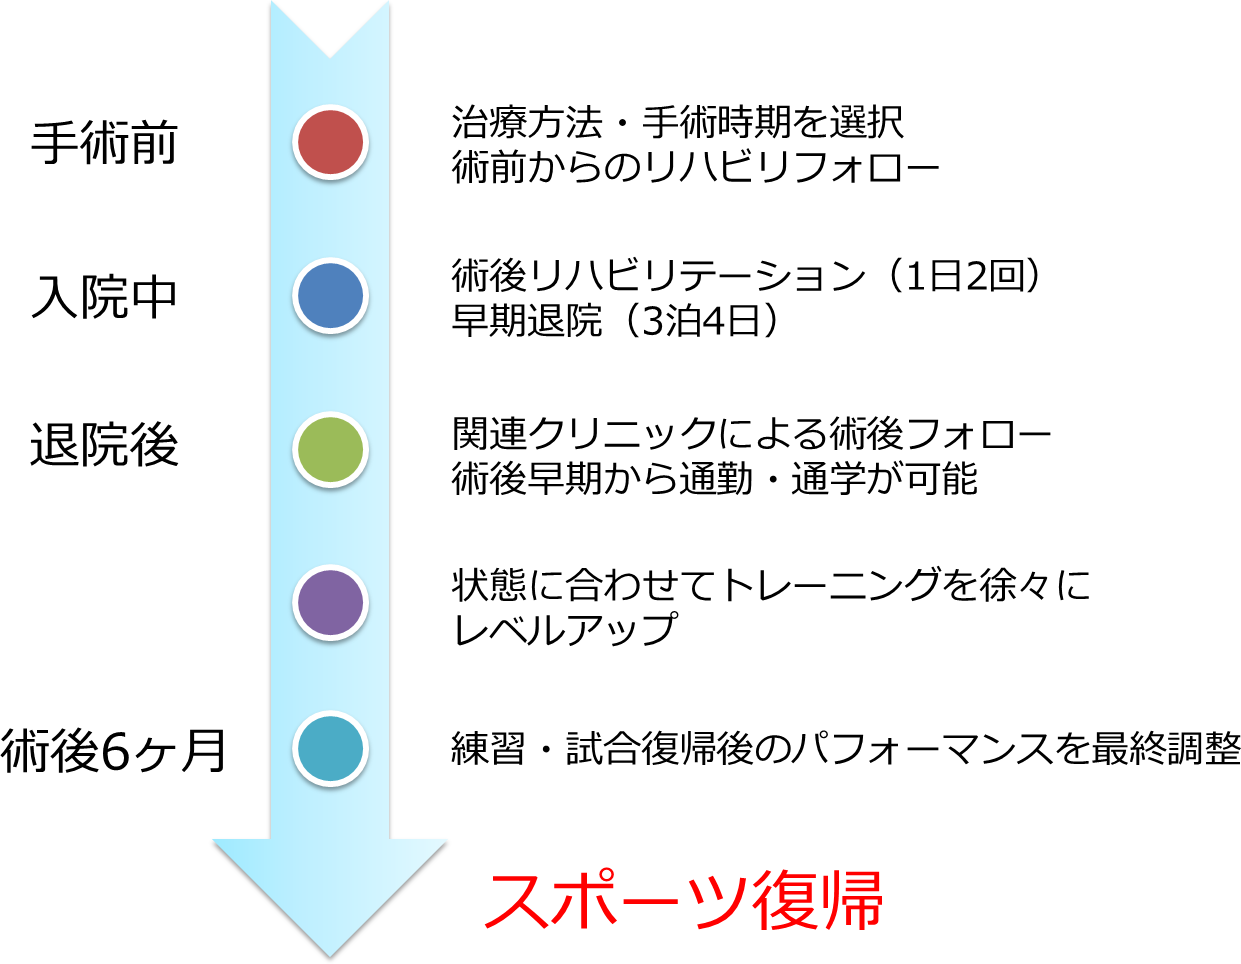

手術前からスポーツ復帰までの流れは?

手術前からスポーツ復帰までの流れは?